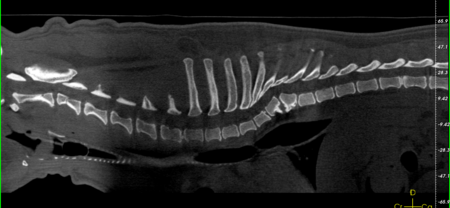

Brachyzephale Hunde leiden häufig an Augenproblemen. In vielen Fällen ist entweder zu wenig Tränenflüssigkeit vorhanden oder die Zusammensetzung des Tränenfilms ist nicht gut. Die Folge sind dauerhaft gereizte Augen, Bindehautentzündungen und Hornhautdefekte, die eine lebenslange Therapie mit Augenmedikamenten nötig machen. Nicht selten sind auch hier kostenintensive Operationen notwendig. Weitere Operationskosten entstehen, wenn die Französische Bulldogge für die Rasse typische Erkrankungen des Bewegungsapparats mitbringt. Vertreter dieser Rasse neigen zu Keil-, Block- und Schmetterlingswirbeln. Eine Folge dieser Anomalien ist häufig ein Bandscheibenvorfall, dessen Diagnose mittels CT und dessen chirurgische Behebung Kosten in Höhe von knapp 4.000 Euro verursachen kann.